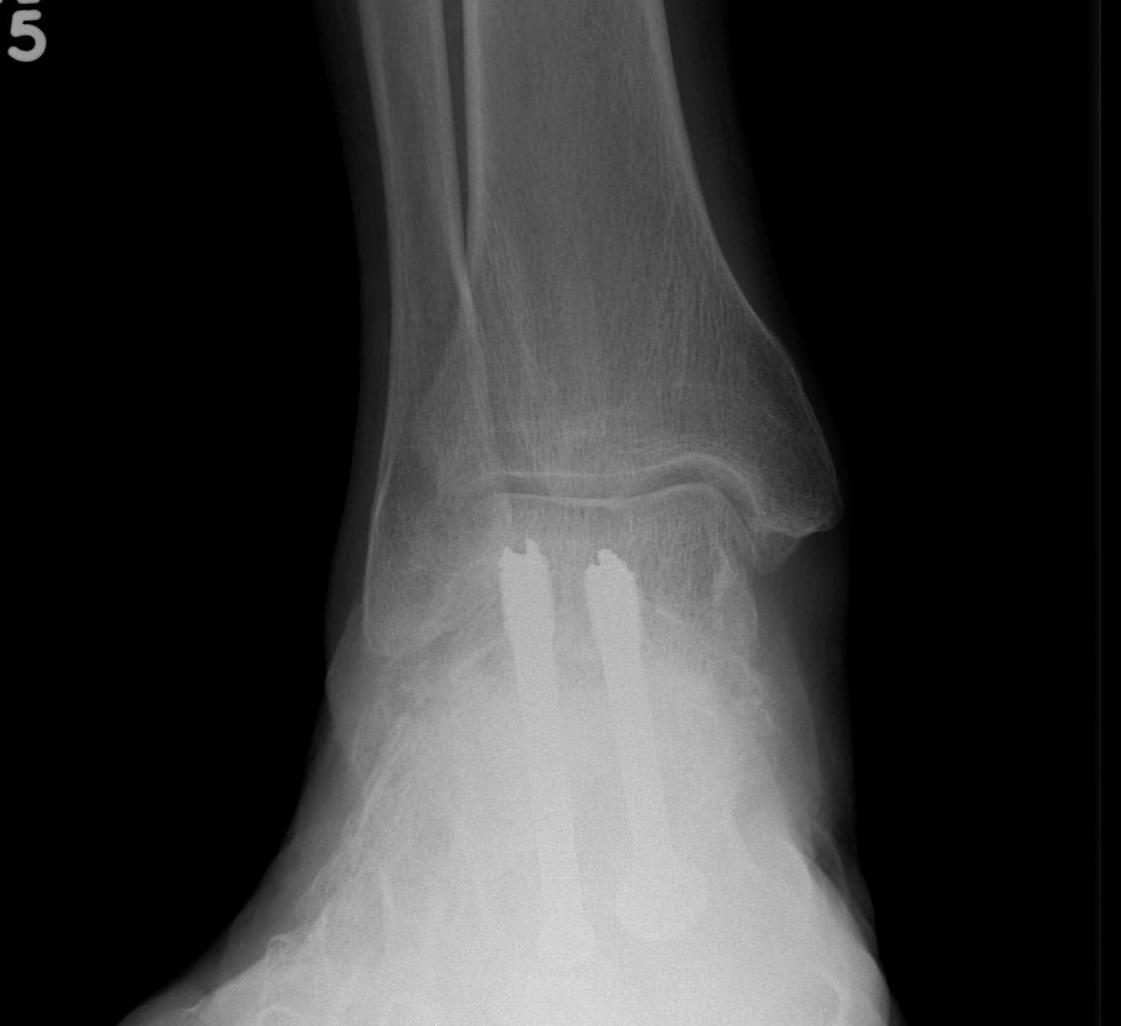

CT

Subluxation of TNJ with advanced STJ OA

TNJ OA with posterior / medial / anterior facet OA of the subtalar joint